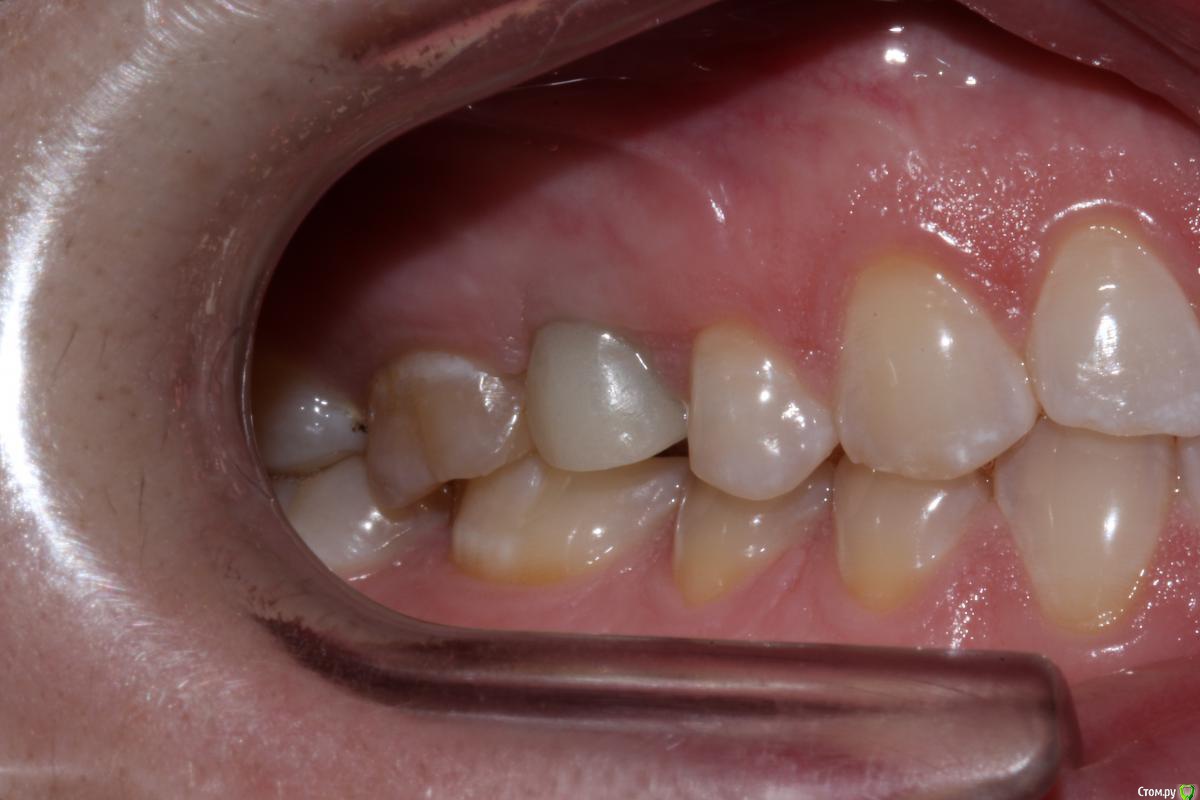

Dr. Khurtsilava Опубликовано 25 октября, 2015 Поделиться Опубликовано 25 октября, 2015 Пациентка обратилась в клинику с жалобами на отсутствие коронки на имплантате 15 в течение года (ставила в другой клинике, клиника закрылась, «голый» Nobel CC остался во рту); наличие дефекта с щечной стороны.Объективно, с щечной стороны обнаруживается дефект альвеолярного гребня в/ч в области имплантата 15 в вестибулярно-язычном направлении; отсутствие коронки на имплантате 15.Манипуляции:1 – забор ССТ с неба конвертной методикой по Зуккелли (спасибо «Доктуру» за это).2 – ушивание непрерывным замыкающим швом Prolene 5-0; лоскут обезжирен – отдыхает в физ. р-ре.3 – в области имплантата внитрибороздковый разрез, ослоение, мобилизация лоскута, деэпителизация сосочков, установка Формирователя Десны, подшивание ССТ, фиксация, ушивание лоскута в области сосочков двойным петлевым швом Prolene 5-0.Рекомендации: гигиена полости рта, мягкая зубная щетка CuraProx 5460, полоскание Curasept 0,2%, солкосерил дентальная адгезивная паста в донорской зоне и зоне реципиента, найз 2т 2р/д утром и вечером 4 дня.На 7 сутки снятие швов, соблюдение рекомендаций.Пациентка по семейным обстоятельствам пропала на пол года, явилась вчера на продолжение лечения.Вот такой вот приятный десневой рекол с врем коронкой) 10 Ссылка на комментарий